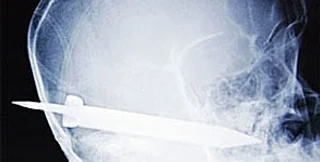

После проведения рентгенографии было установлено, что лезвие ножа имеет длину 13 сантиметров, входит в череп над левым ухом пациента, проходит вниз в полость носа и заканчивается в ротовой полости. Многочисленные крупные сосуды и нервные стволы, расположенные в этой части головы, оказались незатронуты, сообщает medportal.ru.